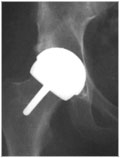

Endoprotezy stawu biodrowego

Rodzaje najczęściej używanych endoprotez stawu biodrowego.